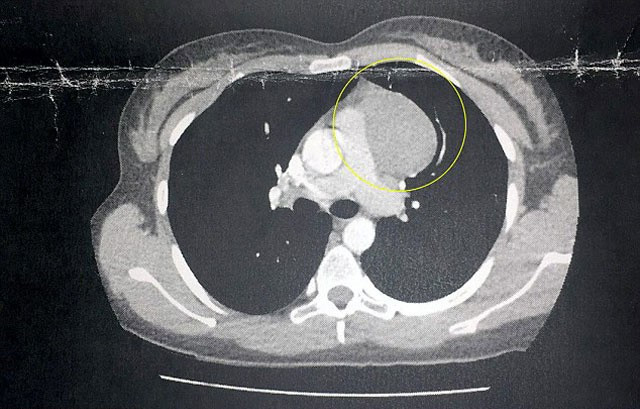

Cildinin tıraştan tahriş olduğunu zanneden Rhiannon Douglas isimli kadın, kanser olduğunu öğrenince şoke oldu. 21 yaşındaki Rhiannon bacaklarında kızarıklıklar fark edince tüylerini tıraş bıçağıyla almasından kaynaklandığını düşündü. Ancak kızarıklıklar bütün vücuduna yayılırken sırt ağrıları da baş gösterince hastanenin yolunu tuttu.

Teşhis konulduğundan beri, genç kadının tümörü kendi kendine büyük ölçüde küçüldü. Rhiannon, vegan diyetinin yardımcı olduğunu düşünüyor.